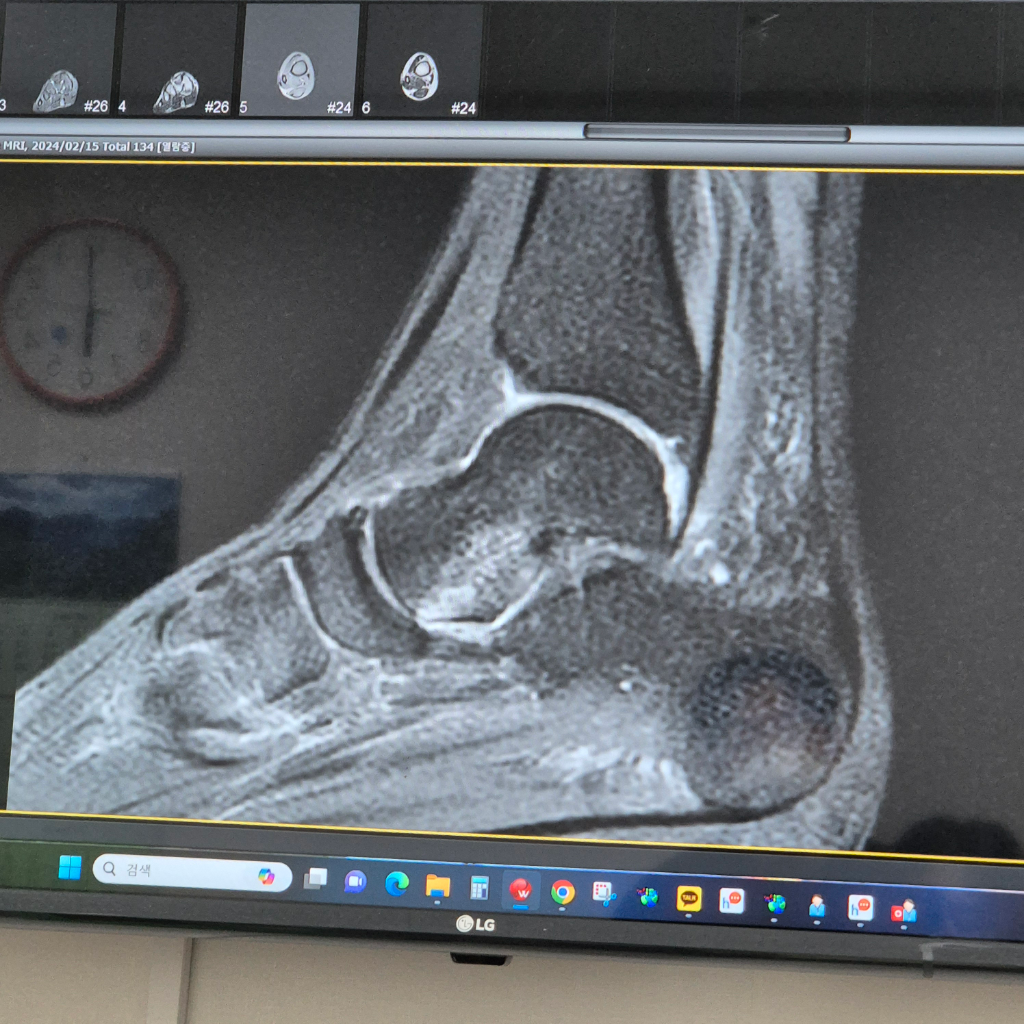

mri 거골 골절진단 상태가 어느 정도인가요?

mri는 15일 찍었어요 반깁스상태인데 오른쪽 발목 안쪽이 걸을때마다 아픈데 언제 쯤 괜찮아질까요?

올려주신 MRI사진상 거골에 경미한 골수부종 의심소견이 보입니다.

하지만 MRI의 다른 시퀀스 사진이 있어 올려주신 사진만으로 진단하기에는 어렵습니다.

사진을 찍으신 병원에서 자세한 MRI 결과 및 주치의의 설명을 참고하시기 바랍니다.